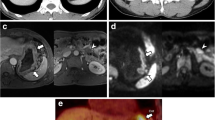

DCE-MRI showing a tumour of the gastric antrum (a) in a 66-year-old female. In the pretreatment scan, the Ktrans (b) was 0.078 min−1, the Kep (c) was 0.237 min−1 and the Ve (d) was 0.347. The tumour was confirmed at biopsy (e). In the posttreatment scan, there was a reduction in tumour size (f), and the Ktrans (g) was 0.070 min−1, the Kep (h) was 0.295 min−1 and the Ve (i) was 0.263. Final pathology (j): intestinal type (Lauren classification), staged as ypT1bN0 (tumour regression grade 1)

DCE-MRI of a tumour of the gastric antrum (a) in a 61-year-old female. In the pretreatment scan, the Ktrans (b) was 0.085 min−1, the Kep (c) was 0.176 min−1 and the Ve (d) was 0.539. The tumour was confirmed at biopsy (e). In the posttreatment scan, the tumour is still visible (f), and the Ktrans (g) was 0.128 min−1, the Kep (h) was 0.297 min−1 and the Ve (i) was 0.455. Final pathology (j): diffuse type (Lauren classification), staged as ypT3N0 (tumour regression grade 3)